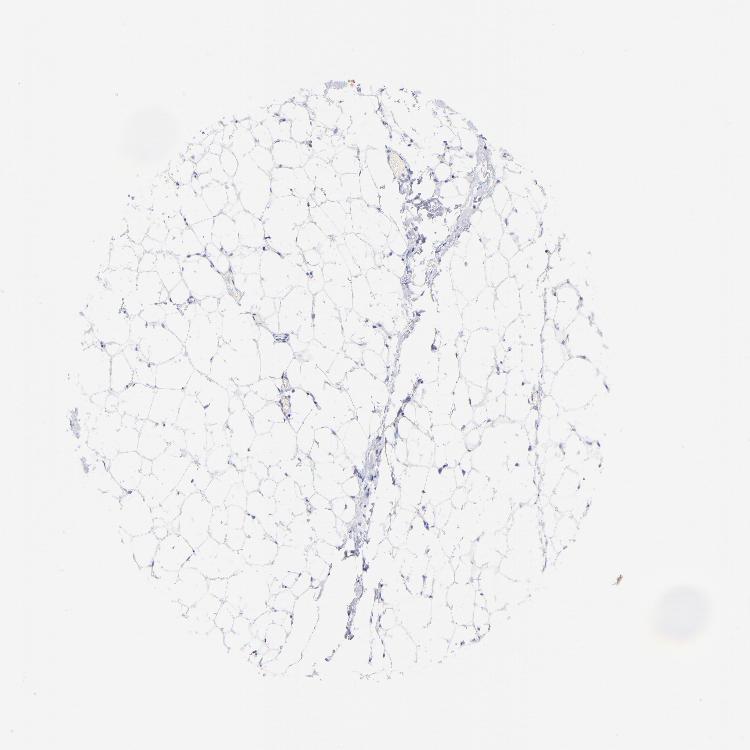

ADIPOSE TISSUE - Antibody stainingi

Antibody staining in the annotated cell types in the current human tissue is reported as not detected, low, medium, or high, based on conventional immunohistochemistry profiling in selected tissues. This score is based on the combination of the staining intensity and fraction of stained cells.

Each image is clickable and will lead to virtual microscopy that enables deeper exploration of all samples and also displays staining intensity scores, fraction scores and subcellular localization as well as patient and tissue information for each sample.

Antibody HPA002465Antibody CAB000031

Adipocytes Not detectedNot detected